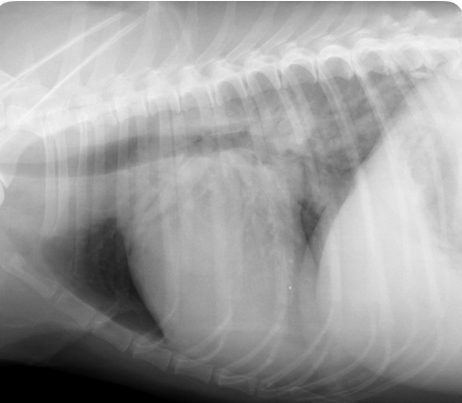

What is going on with this dog heart?

Microcardia

What is going on with this cat heart?